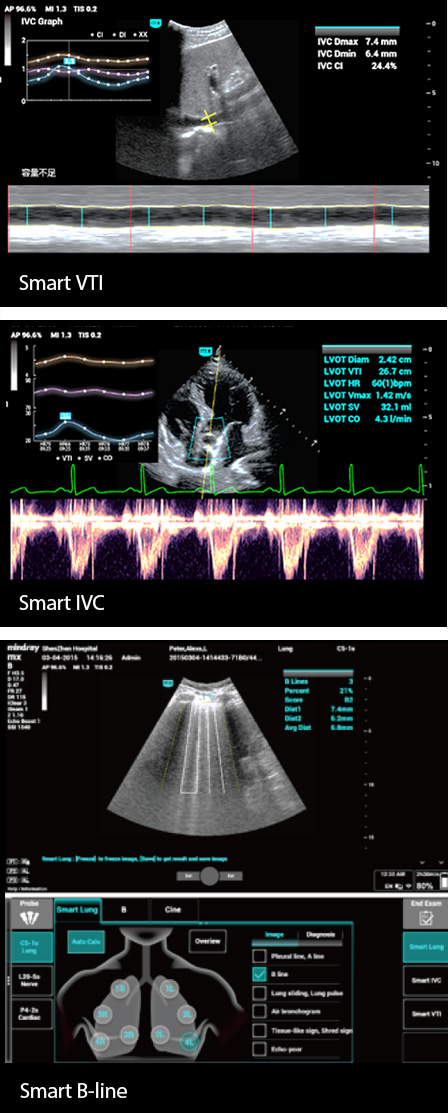

Pati?nten op de intensive care hebben meestal cardiopulmonale, lever- en nierinsuffici?ntie of -falen, en hun vitale functies kunnen op elk moment veranderen, waarbij de lichaamsvloeistoffen bij ongeveer 90% van de ernstig zieke pati?nten snel veranderen. Gastro-intestinale bloeding, ernstige endocriene en metabole stoornissen, verstoringen van het water-elektrolyten- en zuur-base-evenwicht, lever- en nierdisfunctie zijn allemaal veel voorkomende afwijkingen op de IC die tot uiting komen in veranderingen in de lichaamsvloeistoffen.

Daarom zijn nauwgezette vloeistofmonitoring en nauwkeurig volumebeheer van pati?nten van het grootste belang. Echografie heeft echter het voordeel dat het intu?tiever is bij de dynamische beoordeling van de cardiopulmonale functie en de hemodynamiek van pati?nten, en kan IC-medewerkers helpen bij het nemen van tijdige beslissingen over de behandeling en bij het waarnemen van de effecten van de behandeling in realtime.

Daarom zijn nauwgezette vloeistofmonitoring en nauwkeurig volumebeheer van pati?nten van het grootste belang. Echografie heeft echter het voordeel dat het intu?tiever is bij de dynamische beoordeling van de cardiopulmonale functie en de hemodynamiek van pati?nten, en kan IC-medewerkers helpen bij het nemen van tijdige beslissingen over de behandeling en bij het waarnemen van de effecten van de behandeling in realtime.